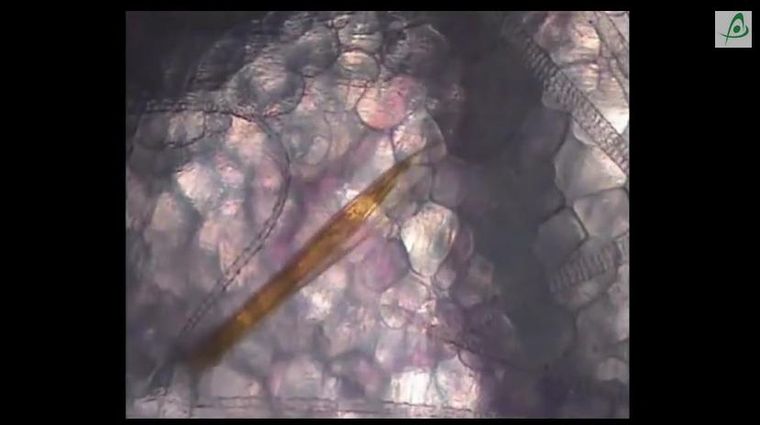

Presentamos a continuación un video sobre la picadura del Anopheles gambiae en mamíferos, filmado utilizando la técnica de microscopía dentro del cuerpo de animales vivos, como ratones anestesiados.

En las imágenes se puede cómo la trompa de estos mosquitos no es rígida, sino que se mueve con mucha facilidad debajo de la piel buscando los capilares adecuados para extraer sangre.

También se puede apreciar que hay partes de la trompa que sirven para perforar la piel, para extraer la sangre y para inyectar la anestesia que también impide la coagulación.